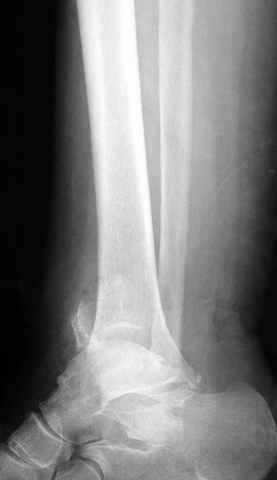

Традиционная техники АО, открытая, с точной репозицией суставной поверхности и жесткой фиксацией, из-за серёзных осложнений, которые

заканчивались ампутацией, уходит в прошлое.

Техника сегодня более щадящая, временные несложные аппараты наружной фиксации: Spanning 2 pin ExFix, Traveling traction для лигаментотаксиса, иначе сокращенные мягкие ткани невозможно восстановить позже.

За последнее 10-12 лет после стабилизации малоберцовой кости, стали применять более усовершенный, сложный, хорошо вам известный метод

Илизарова (кстати наряду с тибиал плато, пилон является одним из показанием по применению аппарата Илизарова при травмах) или Hybrid

Fixator, из минимальных доступов комбинированный метод для восстановления суставной поверхности-фиксация каннулированными

шурупами, создания жесткой системы фиксации до сращения перелома, защита от вальгусной деформации и на место образовавщегося метафизарного дефекта- костная пластика ауто костью или его

синтетические заменители, это сегодняшная тактика лечения.

Дистракция в аппарате или на вытяжение результат - лигаментотаксис, посмотреть бы, как сегодня расположены отломки.